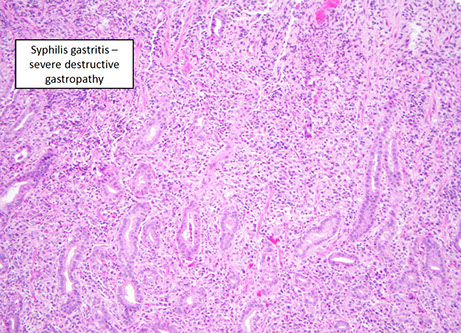

Infectious gastritis (syphilis, CMV, EBV)

- eos may be prominent, but not usually counted

Syphilis

- has a variable appearance, having lots of mixed inflam (similar to autoimmune pangastritis) c gastric gland damage; should do direct IF or immunolabeling if suspected

CMV

not uncommon in inpts, may be mistaken for lymphoma

EBV

- can appear similar to large cell lymphoma in same way that infectious mono simulates leukemia

EBV gastritis - mimics lymphoma [1]